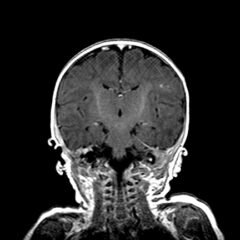

Electronic cigarette (e-cigarette) or vaping associated lung injury (EVALI) cases have increased with the popularity of e-cigarettes in the mostly young, healthy population. Some common symptoms associated with EVALI include shortness of breath and chest pain, and the most common diagnostic imaging findings are organizing pneumonia and diffuse alveolar damage seen on computed tomography (CT). Pneumomediastinum is a known sequela of EVALI.1 In the setting of pneumomediastinum in EVALI, EVALI is a diagnosis of exclusion, so other sources of pneumomediastinum need to be evaluated. EVALI has diverse presentations, and this case is a unique representation of a disease process that is becoming more commonplace with the increase in popularity of vaping. It is important to be aware of the clinical symptoms of EVALI, which can be nonspecific and can include gastrointestinal symptoms along with respiratory symptoms. It is equally important to recognize the diverse image findings of EVALI, which can include subcutaneous emphysema and pneumomediastinum. In this case, pneumomediastinum is seen in EVALI, and the patient was successfully treated with empiric antibiotic coverage, steroids, and conservative measures—making sure to limit any coughing or increases in intrathoracic pressure that can cause worsening of pneumomediastinum.